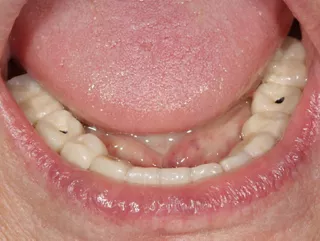

11. The temporary restoration with correct occlusion and jaw relation, at the end of the operation.

16. Display of the finished lower jaw work after osseointegration.